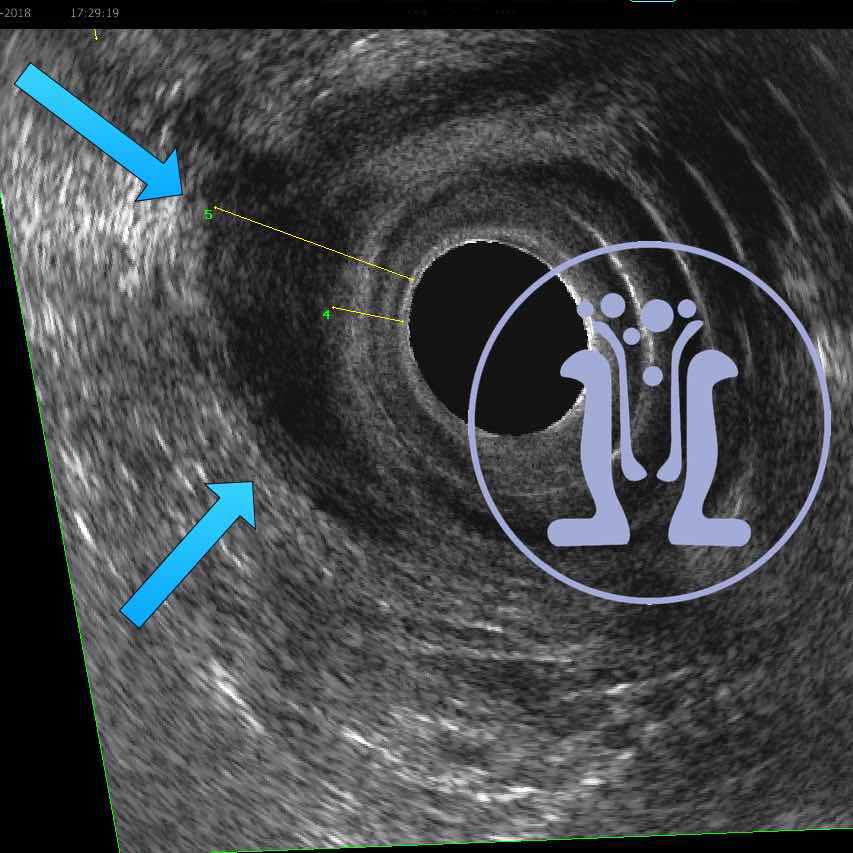

24 09 2018 Το συριγγιο ήταν διπλό

Εγινε παραπομπή ασθενούς από άλλο συνάδελφο για χαρτογραφηση του συριγγίου. Κατά την εξεταση διαπιστώθηκε ότι υπήρχαν δυο συριγγια στην 6η … Περισσότερα